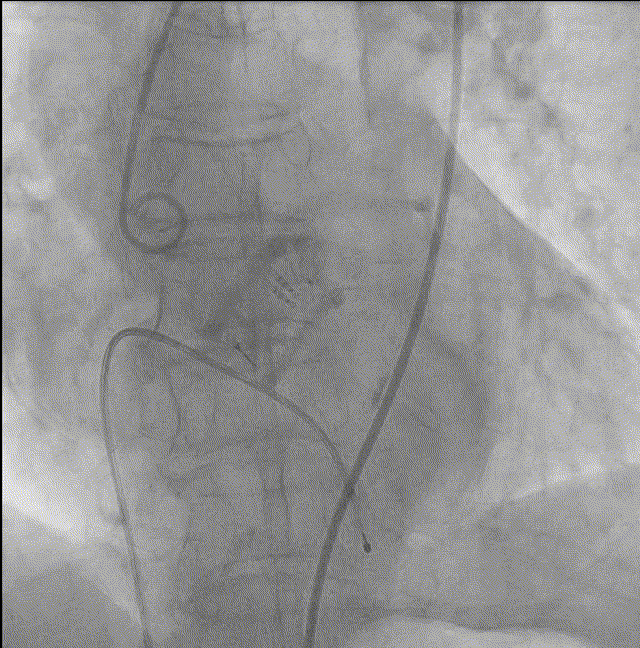

9. Silara A–25mm瓣膜提拉至瓣环水平,反复调整瓣膜位置,形态欠佳,遂用22mm球囊扩张同时充填主动脉环,造影剂显示瓣膜形态及功能良好,完成固化;

10. 最终造影瓣膜位置理想,无反流,微量瓣周漏。